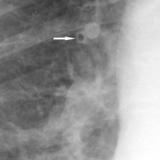

APE 2

Date: 11/05/2005

Views: 2684